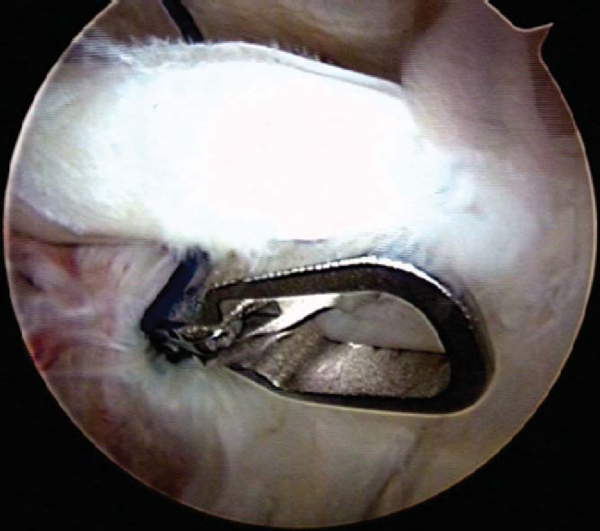

A basket forceps is inserted through the anterior cannulated portal to transect the biceps tendon at the superior labral junction (

Fig. 27-2

). Care is taken to avoid inadvertent damage to the superior glenoid labrum.

Figure 27-2 |